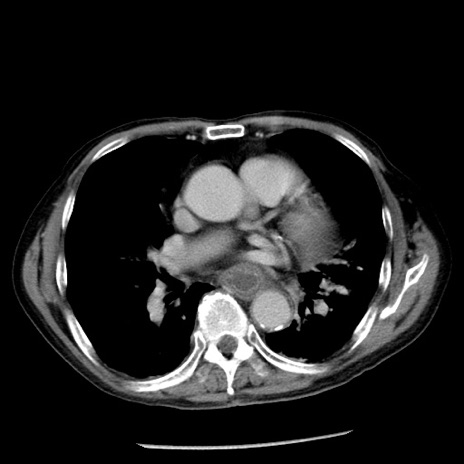

症例26(横断像)

【症例】80歳代男性

【主訴】嘔吐

【現病歴】昨晩2回嘔吐あり、今朝になっても嘔吐あり。来院。

【既往歴】胃潰瘍

【身体所見】意識清明、BT 37.6℃、BP 166/95mmHg、HR 100bpm、SpO2 97%、腹部:平坦・軟、腸蠕動音聴取良好、圧痛なし。

【データ】WBC 21900、CRP 1.46